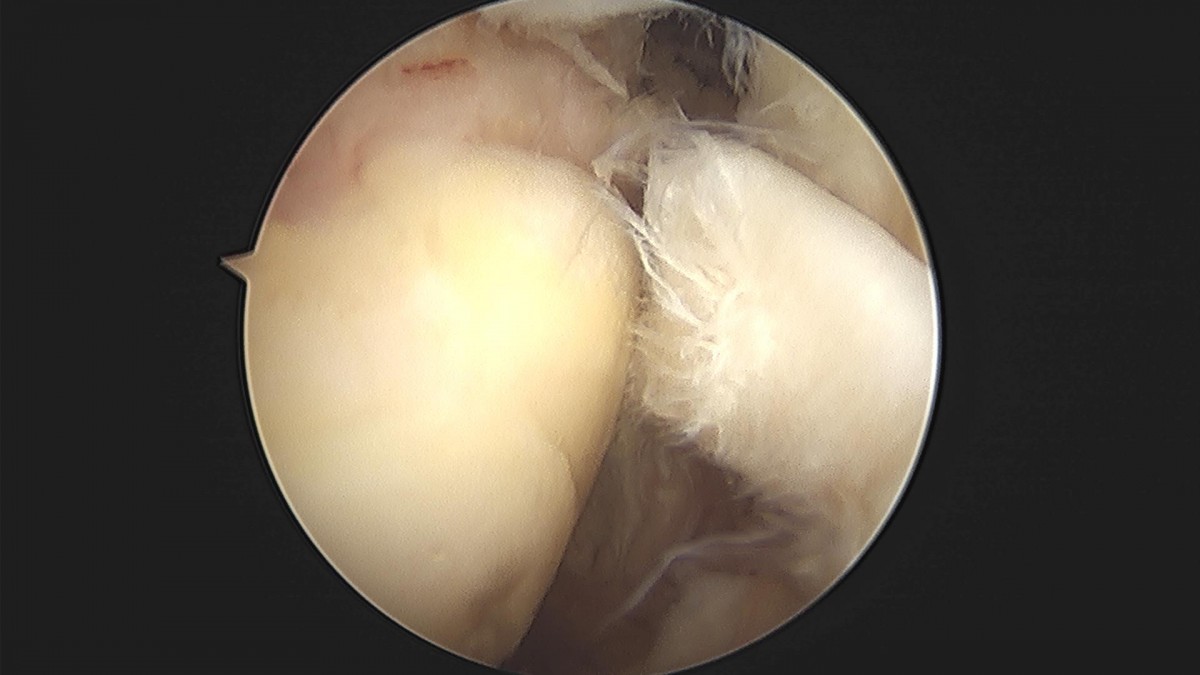

최원락 원장님 어깨 회전근개 봉합술 강신O 환자

f537707b0b9f2537509492404de31ecf_1716863725_06.jpg

f537707b0b9f2537509492404de31ecf_1716863725_1208.jpg

f537707b0b9f2537509492404de31ecf_1716863725_1698.jpg

f537707b0b9f2537509492404de31ecf_1716863725_22.jpg

f537707b0b9f2537509492404de31ecf_1716863725_2621.jpg

f537707b0b9f2537509492404de31ecf_1716863725_3103.jpg

f537707b0b9f2537509492404de31ecf_1716863725_3604.jpg

f537707b0b9f2537509492404de31ecf_1716863725_4421.jpg

f537707b0b9f2537509492404de31ecf_1716863725_488.jpg

f537707b0b9f2537509492404de31ecf_1716863725_5328.jpg